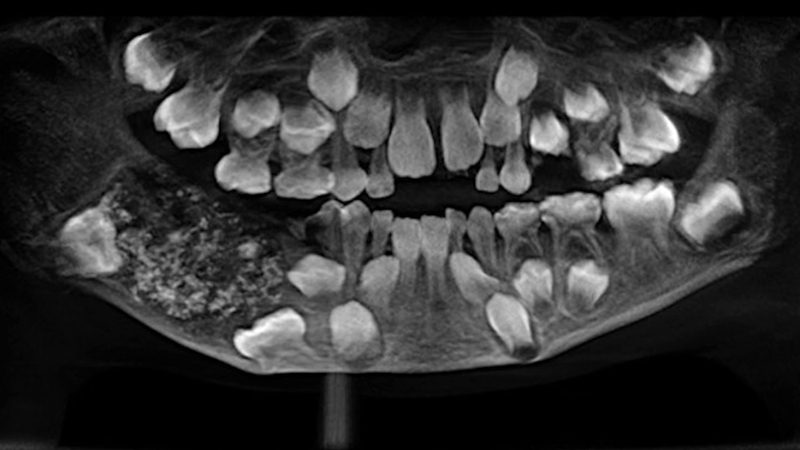

医院的医生拍了一张x光片,显示出肿块内有许多小的未发育的“牙齿”。口腔颌面外科教授森提尔内森说:“CT扫描显示,多颗“牙齿”将恒牙推到了下颚。我们计划采取保守治疗,不切除颌骨。”他补充说,16年后,这名男孩将需要植入两颗恒磨牙。

Saveetha牙科医学院的一组外科医生从一名7岁男孩的右下颚切除了一个包含526颗“牙齿”的肿块。这个近200克重的庞然大物里面有许多细小的牙齿,还有几颗中、大牙齿。